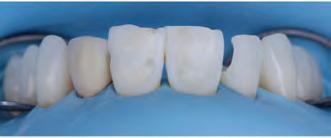

A 31-year-old woman presented with cosmetic concerns regarding her smile and requested a conservative enhancement. After clinical and radiographic analysis, digital 35mm photographs were taken and reviewed by the restorative clinician, technician, and surgeon (Fig 1). A digital impression was taken of the maxillary and mandibular arches using an intraoral scanner (Trios 3, 3Shape; Fig 2), and a smile design was developed with NemoSmile Design 3D software (Nemotec; Fig 3a). This allows for a facially driven smile frame to be created using reference lines of facial and smile proportions and natural teeth shapes and textures from the digital library (Fig 3b).

After developing the simulated mock-up, a 3D-printed resin model was created using CAD software (Fig 4a), and a clear PVS matrix (Exaclear, GC America) was fabricated to replicate the printed diagnostic wax-up using a nonperforated tray (Fig

Fig 1 Preoperative clinical views of a 31-year-old woman presenting with diastemas and limited tooth visibility. (top) Portrait. (center row) Intraoral views. (bottom row) Smile.

4b). This matrix was used to create an intraoral motivational mock-up with bis-acryl composite (Luxatemp Ultra, DMG). This additive mock-up provides the interdisciplinary team with an intraoral translation for evaluation (Fig 5). Upon evaluation of the digital smile frame and the clinical translation, it was determined that multiple esthetic and restorative requirements were necessary for an optimal biologic framework, and the interdisciplinary team determined the best sequence for these procedures. The patient was presented with the interdisciplinary treatment possibilities that included restoring the maxillary anterior teeth and premolars with a minimally

invasive preparationless procedure or with less conservative veneer preparations. The restorative materials discussed included injectable resin composites and ceramic (ie, feldspathic, pressable, machinable). For an optimal biologic framework and health, it was determined that connective tissue grafting would be necessary for treatment of the recessiontype defects on the maxillary left central and lateral incisors, canine, and premolars. The patient opted for the conservative preparationless composite veneers using the injectable resin technique followed by a connective tissue surgical procedure using the tunneling technique.